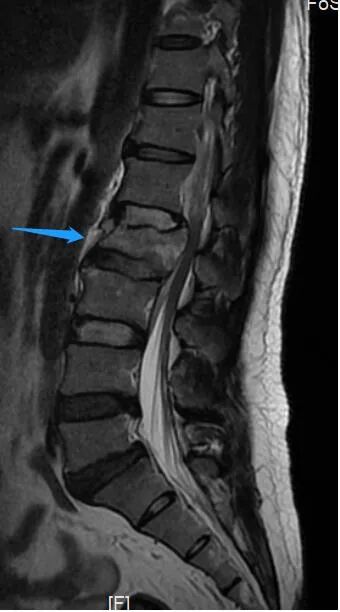

手术后当天,姚某右下肢已可轻微活动,经过1月余的专科康复后,姚某已可拄拐下地站立。他激动地说,“我以为自己将永远躺在床上了,想不到医生还能让我站起来,非常感谢医护人员高超技术和精心照顾。” 腰椎术前X线侧位片 术前磁共振 术前磁共振显示神经明显受压 姚某术后恢复情况 薛厚军副主任医师指出,脊柱骨折是临床常见脊柱损伤,发病群体是青壮年,指的是因外力对脊柱骨质造成连续性的破坏、高处坠落、车祸等高能量损伤是导致脊柱骨折的主要原因。对于严重的脊柱爆裂性骨折,可以造成脊髓或神经的损伤,导致肢体运动感觉障碍或者瘫痪,严重影响病人的生存及生活质量。所以,只要条件允许,应尽早手术治疗。 随着科技的进步以及人们自我保护意识的提高,近年来脊柱骨折的病人已有所减少,但对于其引起的严重后果我们仍不能忽视。建议广大民众出现脊柱骨折后要就近在有实力的医院诊治,搬动要严格轴线平抬,避免二次伤害,以免延误病情。